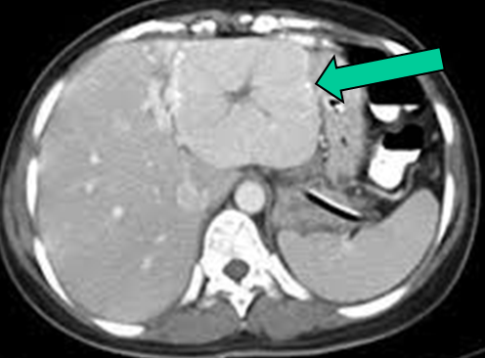

QARACİYƏR ABSESİ

N.Y.Bayramov, R.A.Məmmədov

Tərifi

Abses qaraciyər toxumasında nekroz, infeksion iltihab və septik əlamətlərlə xarakterizə olunan xəstəlikdir.

Diaqnostikası

Dəqiqləşdirmə

Abses diaqnozunu dəqiqləşdirmək üçün klinik əlmətlərlə yanaşı görüntüləmə və laborator müayinələr aparılmalıdır. Yerli və ümumi sepsis əlamətləri ilə yanaşı USM və ya tomoqrafiyada qaraciyərdə abses boşluğun görünməsi diaqnozu dəqiqləşdirir. Absesdə qaztörədən bakteriyalar olduqda və ya bağırsağa açılarsa içərisində qaz görünür (25%).

Diaqnostik əlamətləri:

• Ağrı, hepatomeqaliya, hərarət, septik əlamətləri

• Laborator septik əlamətlər

• Görüntüləmədə destruktiv ocaq

Şəkil 2. Qaraciyər absesində müalicə və proqnoz